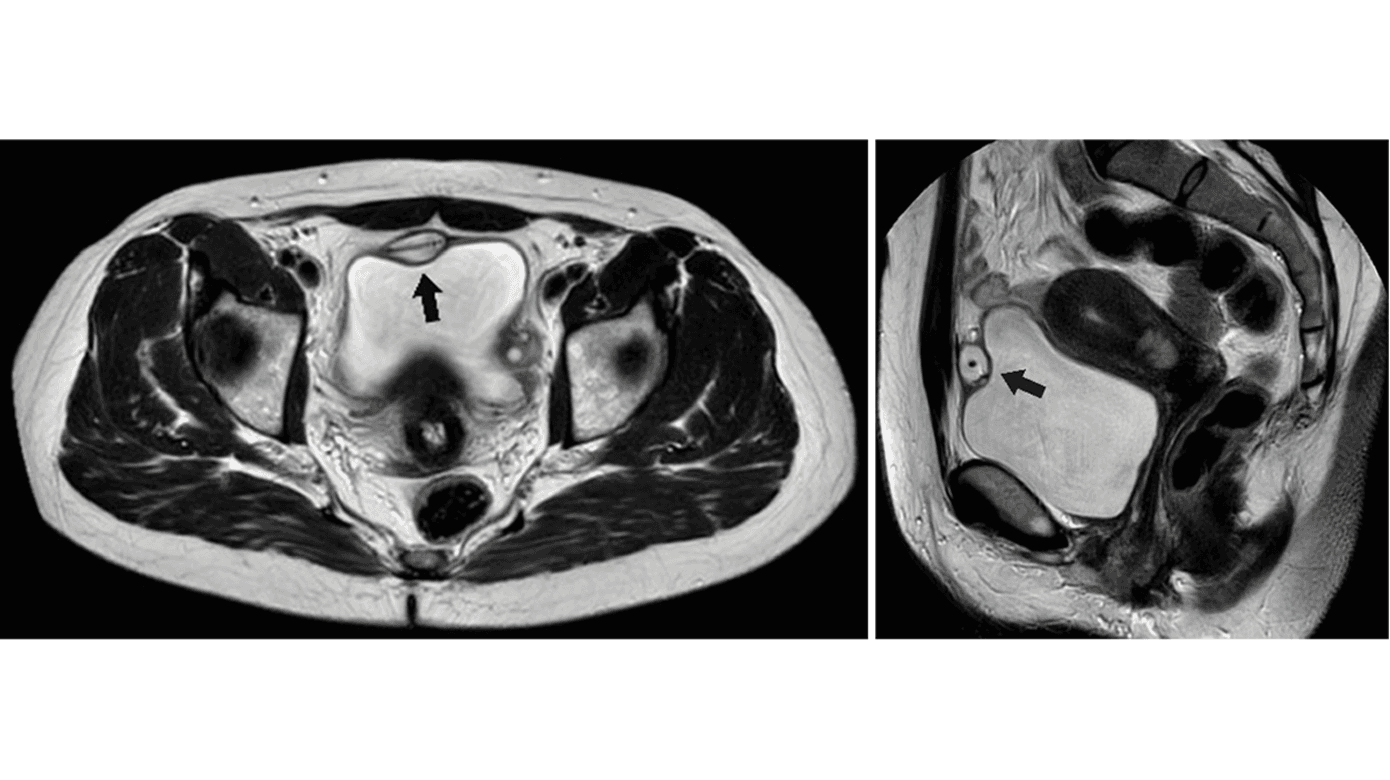

En 47-årig kvinde fik ved helkrops-MR-skanning påvist en 2 × 3 cm stor cyste i blærevæggen. Cysten indeholdt proteinholdig væske og et fremmedlegeme. Kvinden fik som 33-årig ukompliceret opsat en kobberspiral, men ønskede den fjernet ca. halvandet år efter, da hun havde graviditetsønske. Hun erfarede at være gravid, inden spiralen blev fjernet, hvorfor egen læge henviste til en gynækolog, som ikke kunne se spiralen, men bekræftede tidlig graviditet. Fødslen af en rask datter var ukompliceret. Ingen havde set kobberspiralen i forbindelse med UL-skanning, og en ny hormonspiral, som blev opsat i 2014, var fortsat in situ. Der havde været enkelte tilfælde af blærebetændelse, men ellers ingen gener.

På en MR-skanning sås hormonspiralen velplaceret i uterus, mens kobberspiralen befandt sig foran urinblæren og delvist i blærevæggen.